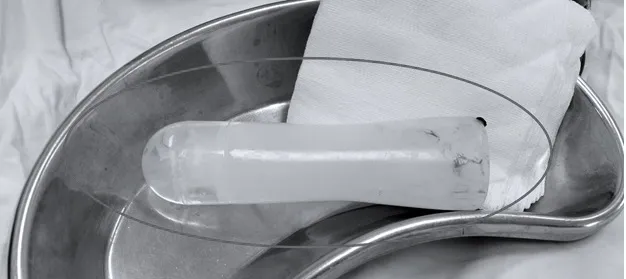

Sau khi thăm khám và chụp X-quang, bác sĩ xác định dị vật nằm sâu trong trực tràng. Người bệnh được gây mê nội khí quản để ê-kíp phẫu thuật lấy dị vật qua đường hậu môn. Kết quả ghi nhận, dị vật là một chai gel rỗng, không có điểm giữ bên ngoài nên dễ dàng trôi sâu qua hậu môn, gây đau đớn.